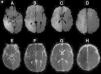

A las 48h de comenzados los síntomas, el paciente agregó paresia crural izquierda y acentuó el deterioro del sensorio. Dada esta sintomatología, y con el fin de reevaluar los hallazgos tomográficos, se efectuó una resonancia magnética (RM), que demostró una franca restricción en secuencia de difusión (DWI) y mapa coeficiente aparente de difusión (ADC) en la lesión corticosubcortical frontoparietal derecha y frontal izquierda, acorde con el diagnóstico de isquemia aguda (fig. 2). Ante estos hallazgos, se decidió repetir el examen Doppler, que nuevamente se mantuvo dentro de parámetros normales.